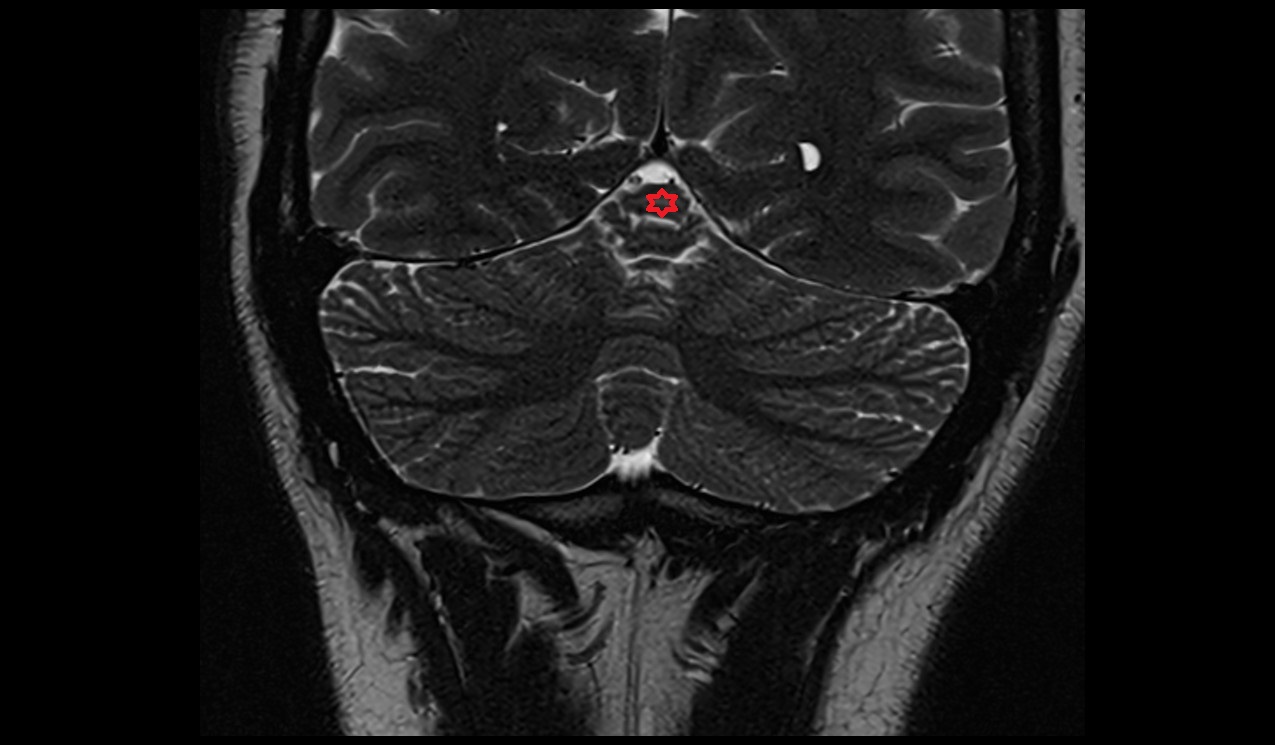

- Cerebellum